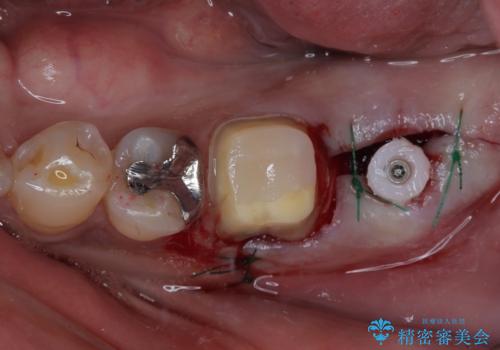

- 食事などで噛んだ時に奥歯が痛むとのことで来院された患者様です。

レントゲン写真より、一番奥の歯の根尖部に大きな病変(炎症により骨が溶けている状態)が認められたため、根管治療を行うこととしました。

根管治療後に痛みは一次消退しましたが、半年ほど経過しても病変は改善しておらず、歯根が破折している状態となっていました。

歯根が破折した歯は抜歯となるため、抜歯して病変の部分に骨が回復するのを待って、インプラントによる補綴治療を行うこととしました。

インプラント治療まで待機している間に、手前のむし歯処置されている歯が強い痛みに襲われ、確認したところ、既に神経組織が壊死している状態であったため、根管治療を行い、インプラント部と合わせて補綴治療を行いました。